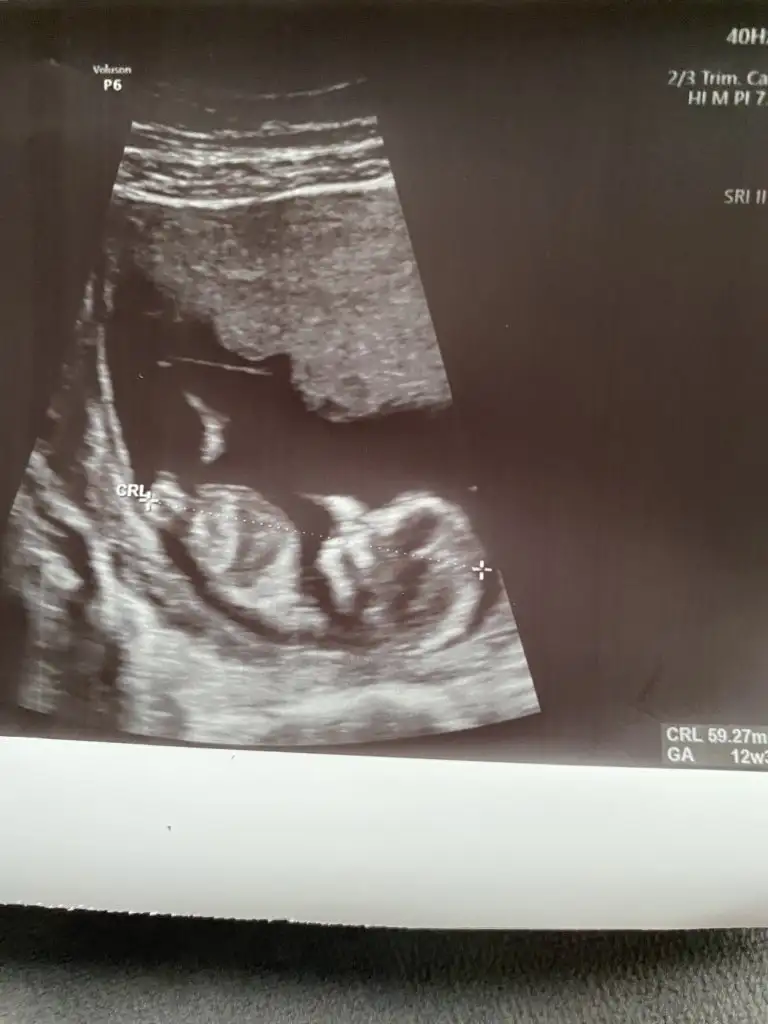

Ikra meyra 12+3 ama dr göremedi net sizin tahmininiz var mıı

Eklentiler

• AA2EEB5F-114E-46A9-8A68-90EF4DA55D4A.webp

24,6 KB · Görüntüleme: 61

• 974C7258-749E-4A4A-87AE-CDDC3E9370B7.webp

23,6 KB · Görüntüleme: 51

• B1506CB2-3341-4227-B8F3-C06147BE779C.webp

13,9 KB · Görüntüleme: 54